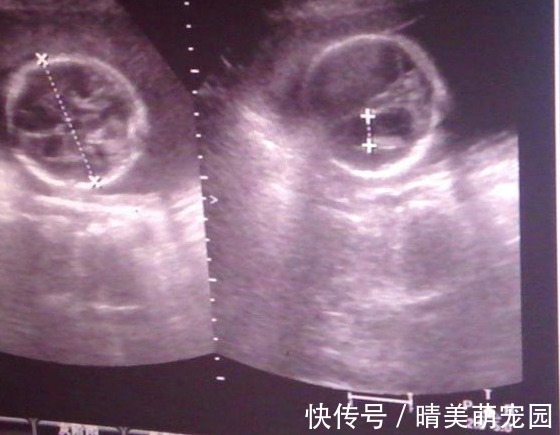

胎宝宝的生活的大人一样,同样离不开吃喝拉撒。“吃喝”是通过脐带传送满足对营养物质的需求,这一点无需强调。但是,除了丰富多彩的运动生活,妈妈们是不是也很好奇,胎儿会不会有大小便行为呢?如果有,那这些大小便跑到哪里去了呢?可以很确定的说,“小大人”也是有大小便的哦!但是,说到这些排泄物的去处,就有点大煞风景了。因为不断的吞吐羊水,所以胎宝宝也会有尿液产生,大概会在9周左右开始,胎儿会产生尿液,而这些尿液会被排放到羊水里面,最终再被自己“回收利用”哦!虽然这样的情况听起来有点小恶心,但其实胎儿生活在妈妈的肚子里面,他的尿液跟食用五谷杂粮的成人不同,是不会对身体产生危害的哦!

与尿液一样,胎宝宝既然在不停的吸收营养物质,那么也是会有排泄物产生的,虽然不是真正意义上的大便,但是那种深绿色的粘稠排泄物就是胎儿的粪便,也叫做胎便。正常的胎儿不会在妊娠期间排便,他们会将这种绿色粘稠物储存在肚子里,出生之后两三天左右就会排干净。胎儿的一切活动都是在羊水中进行,所以,与干净的尿液不同,一旦在孕期排出胎便,羊水就会被污染,会对胎宝宝的生命造成威胁。所以,孕期的宝妈们应该按时进行产检,以免胎儿在肚子里发生危险。